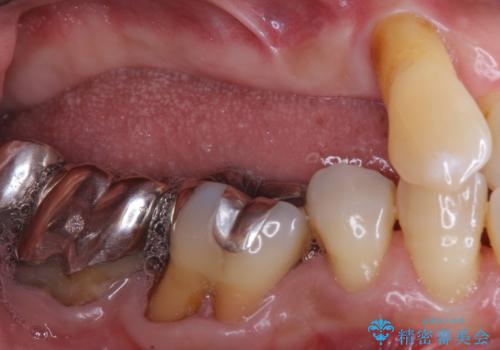

精査したところ右下の奥歯も歯周病により保存不可能な状態でした。

なるべく予算を抑えたいとのご希望から、上顎は入れ歯、右下臼歯部はインプラントによる治療を行いました。

インプラントの種類:スプラインツイスト